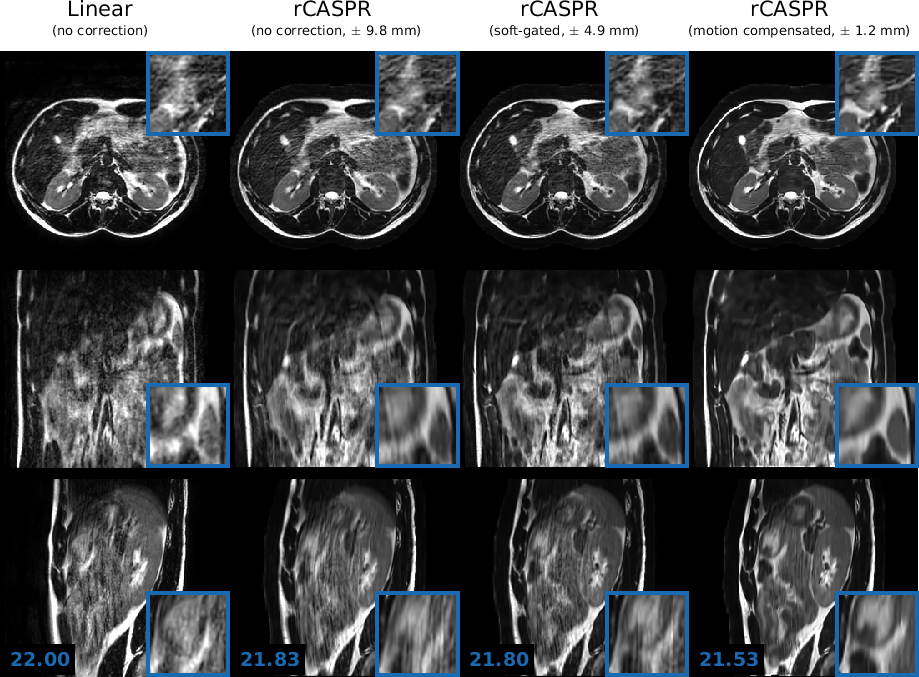

The comparison of image quality in two out of the eight volunteers are shown in Figures 8-7. The results of two other volunteers are shown in Supporting information I. Figure panels A-D show the linear, rCASPR, soft-gated rCASPR and motion compensated rCASPR reconstructions. Note that the soft-gated and motion compensated rCASPR are reconstructed at the exhale position. Zoom images of regions of interest are shown in blue boxes. Blue numbers at the left bottom display the gradient entropy calculated from the entire image. In general, image quality slightly increases when changing the sampling scheme from linear to rCASPR. The addition of soft-gating to rCASPR further increases the image quality. The largest improvement in image quality is observed when transitioning from no correction to the motion compensated image reconstruction.

Figure 8: Volunteer 1: Comparison of image quality in in T2subscript𝑇2T_{2}-w free-breathing 3D turbo spin echo scans for linear, rCASPR, soft-gated rCASPR and motion compensated rCASPR. For all the reconstructions the residual peak-to-peak motion was estimated using the 4D-MRI. For rCASPR the residual motion was ±9.8​m​mplus-or-minus9.8𝑚𝑚\pm 9.8\ mm, soft-gating rejected 50%percent5050\% of the data such that the residual motion was ±4.9​m​mplus-or-minus4.9𝑚𝑚\pm 4.9\ mm and motion compensation had residual intrabin motion of ±1.2​m​mplus-or-minus1.2𝑚𝑚\pm 1.2\ mm. The numbers in left bottom corner indicate the global gradient entropy. Blue boxes present zoomed regions. Acronyms: rCASPR = rewound cartesian acquisition with spiral profile ordering.

The groupwise average gradient entropy was 22.31±0.07plus-or-minus22.310.0722.31\pm 0.07 for linear, 22.20±0.09plus-or-minus22.200.0922.20\pm 0.09 for rCASPR, 22.14±0.10plus-or-minus22.140.1022.14\pm 0.10 for soft-gated rCASPR and 22.02±0.11plus-or-minus22.020.1122.02\pm 0.11 for motion compensated rCASPR. Supporting Information II shows a video of the motion compensated rCASPR reconstruction warped with the DVFs for all the volunteers.